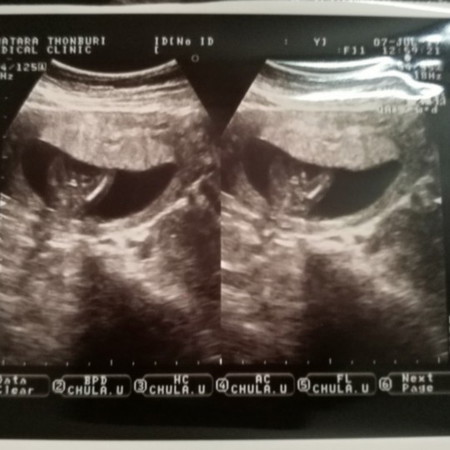

เพศ

แบบนี้ ผู้หญิง หรือผู้ชาย ค่ะ

คุณหมอไม่ได้บอกหรอคะ ถ้าให้เดาคิดว่าชายนะคะ

เหมือนมีกระปู๋เลยคะ